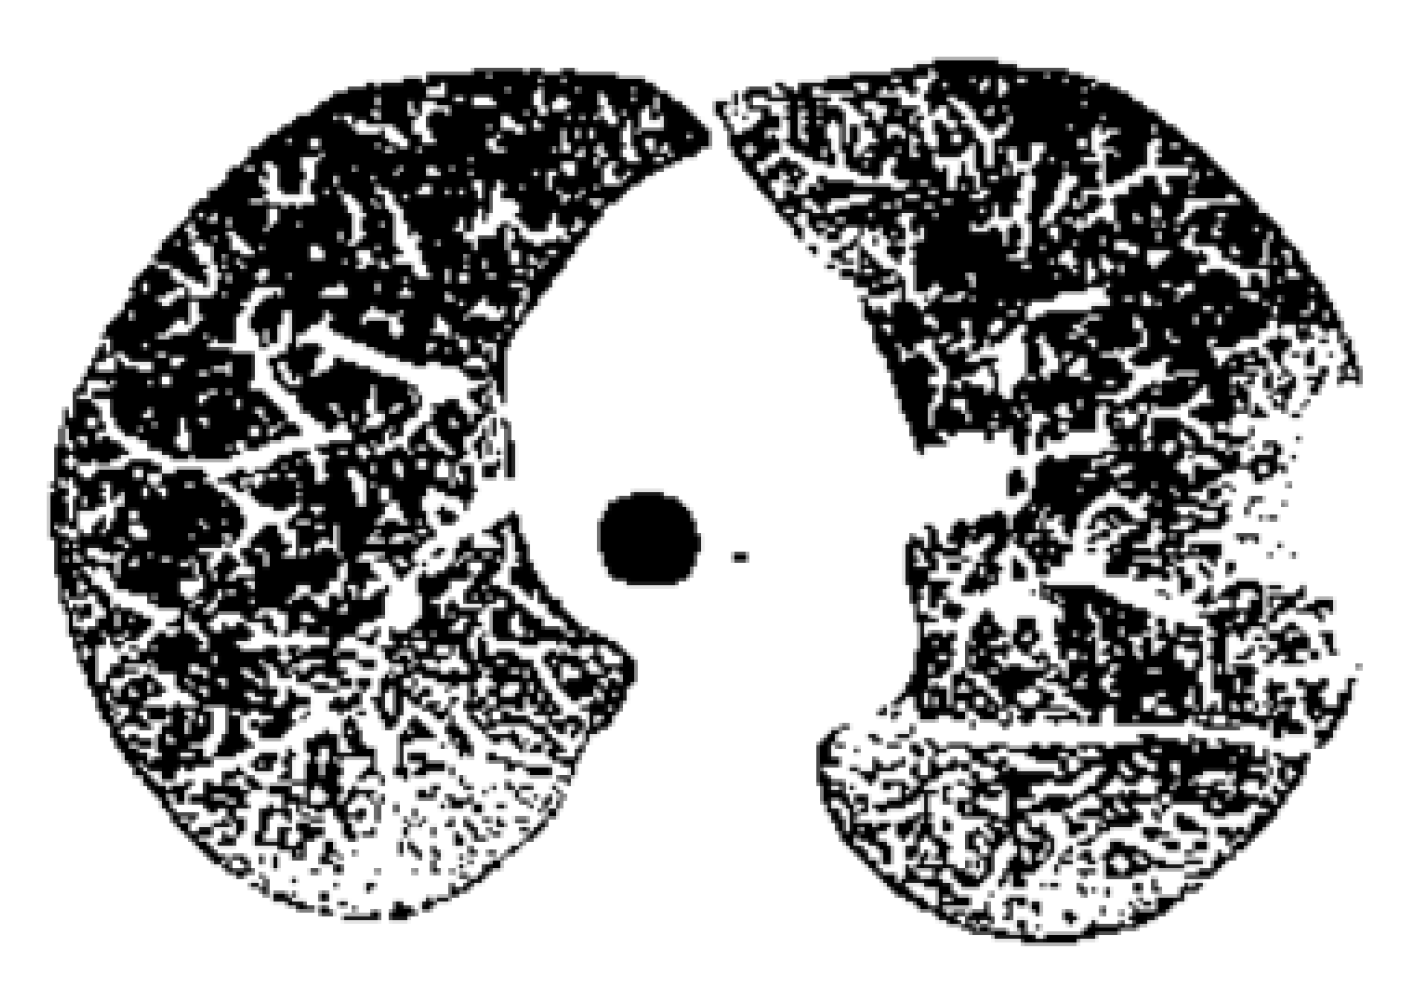

Figure 22 is the binary version of the COVID-19 lung image. Figure 23 represents the box-count algorithm application for the COVID-19 lung image.

Figure 22 is the binary version of the non-COVID-19 lung image. Figure 23 represents the box-count algorithm application for the COVID-19 lung image.

Figure 22. Binary version of the non-COVID-19 lung image.